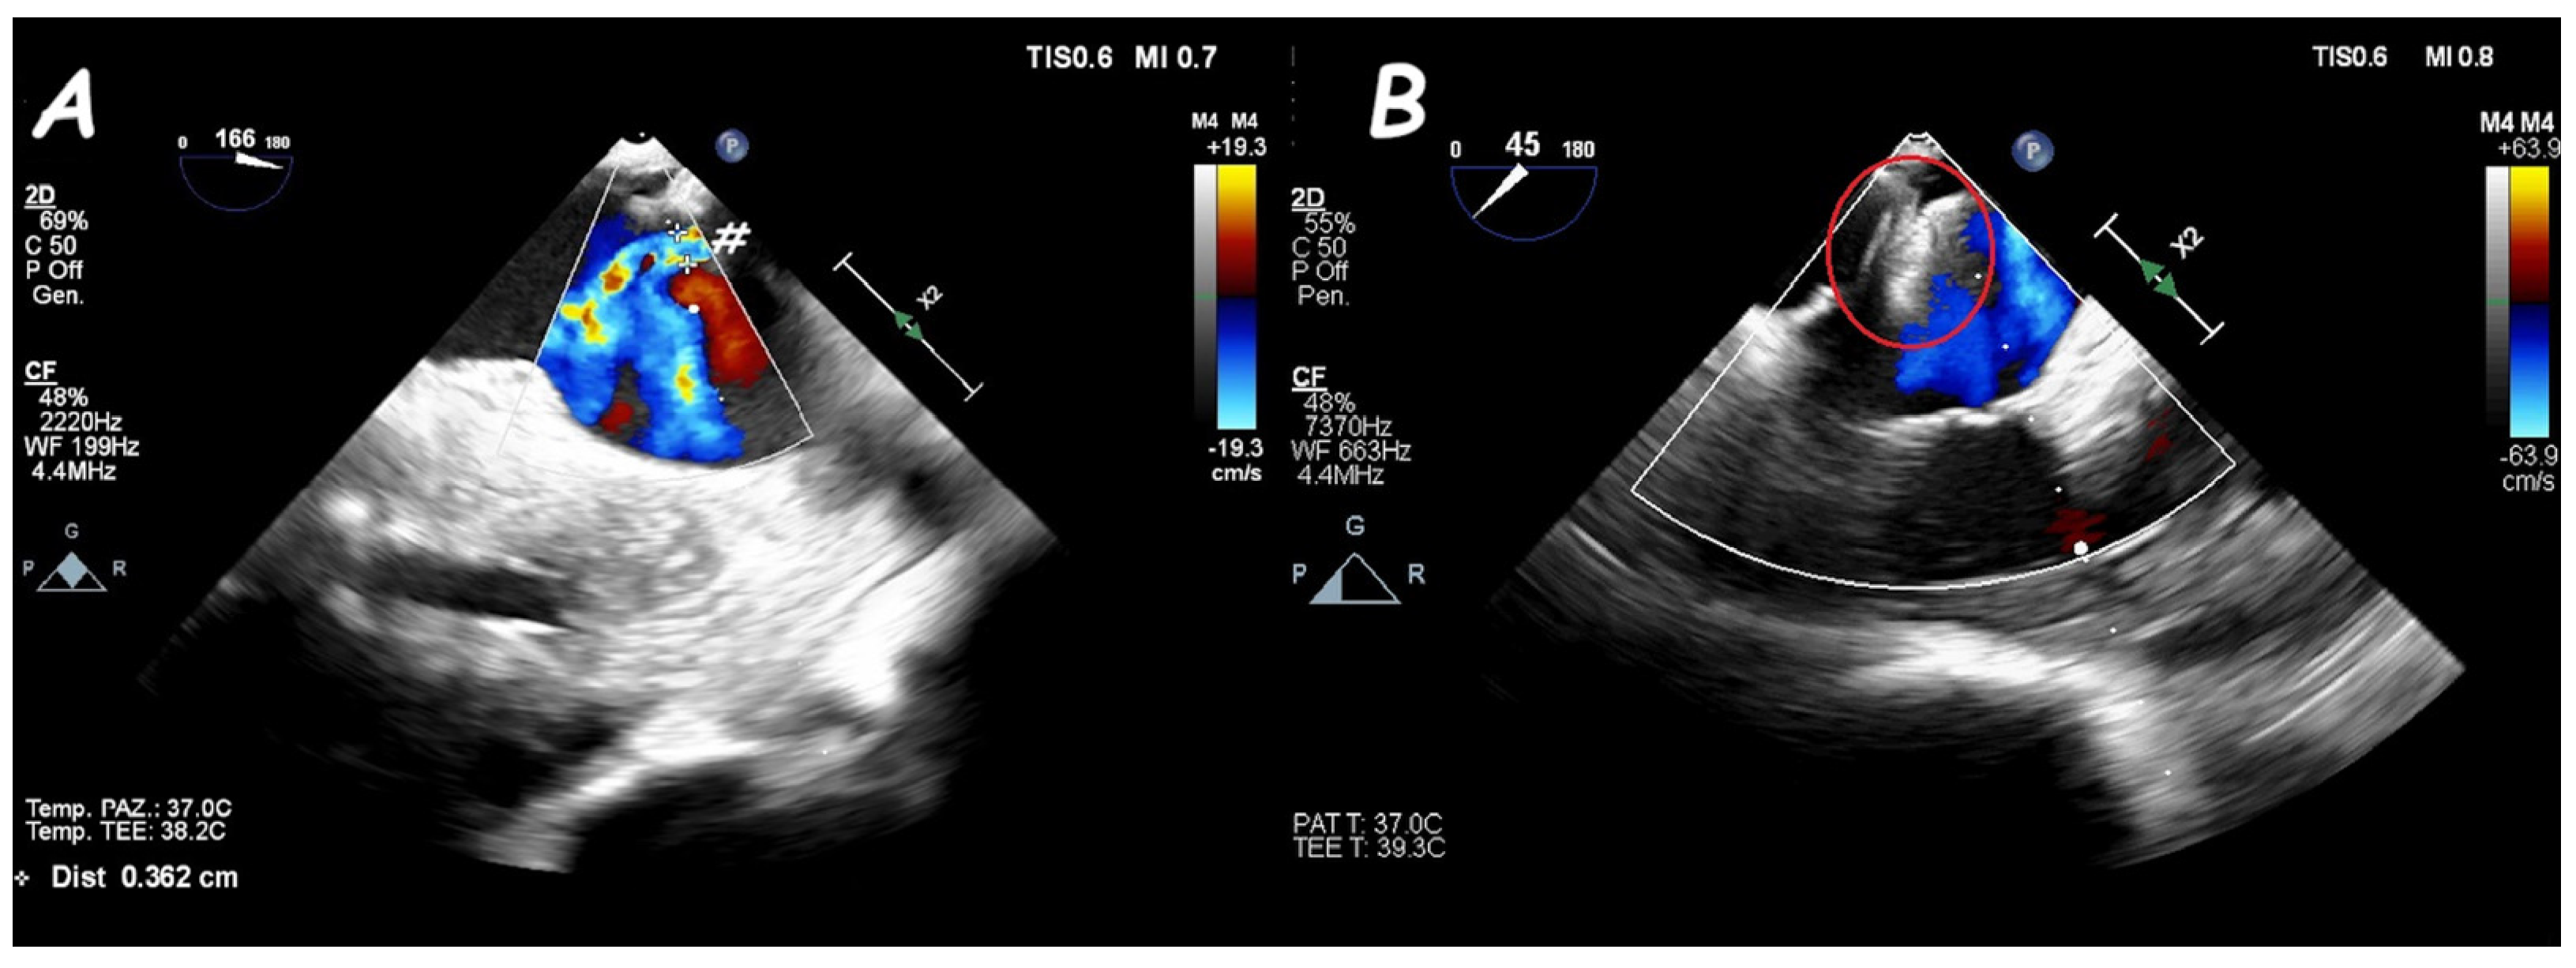

6. Ruptured Sinus of Valsalva Closure